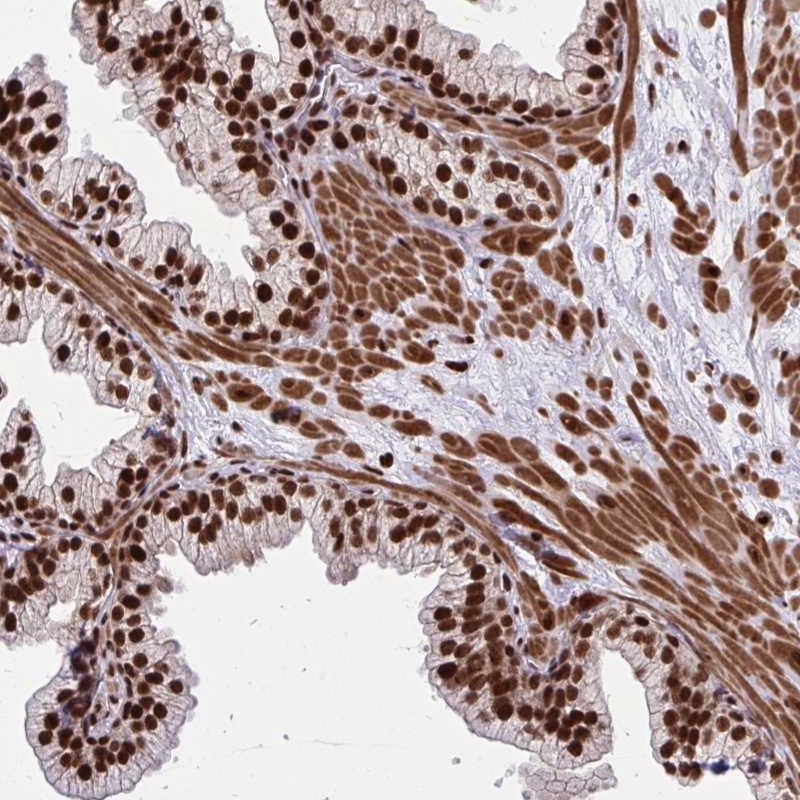

Immunohistochemical staining of human prostate shows strong nuclear positivity in glandular cells.